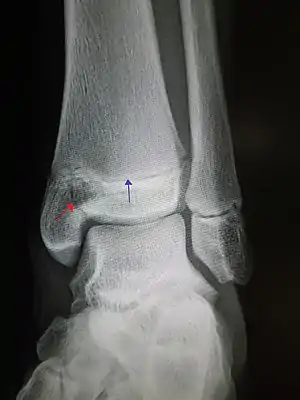

An X-ray of the left ankle showing a Salter–Harris type III fracture of medial malleolus. Red arrow demonstrates fracture line while the blue arrow marks the growth plate.

• Type III – A fracture through growth plate and epiphysis, sparing the metaphysis:[9] 8% incidence